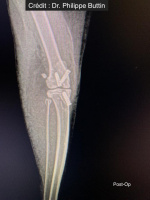

Radiologické snímky